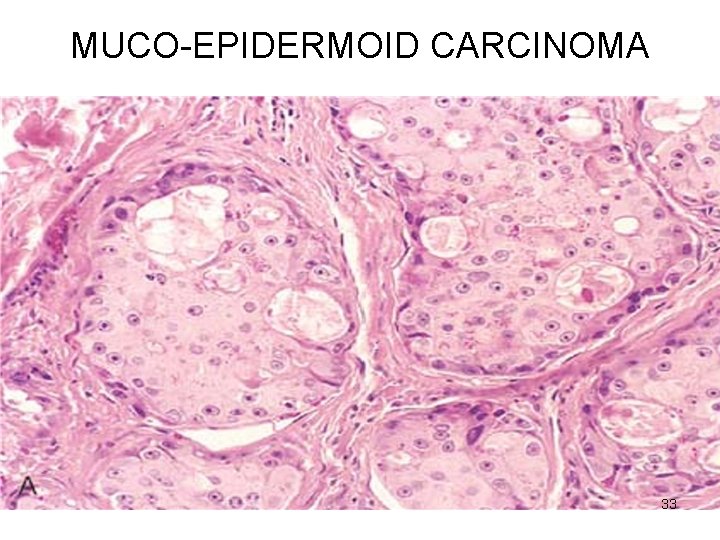

MUCO-EPIDERMOID CARCINOMA Microscopy • Mixtures of three cell types arranged in cords, sheets, cystic 1. mucus-secreting cells 2. intermediate cells (hybrid) squamoid features with small to large mucusfilled vacuoles 3. squamous cells 32

MUCO-EPIDERMOID CARCINOMA 33

MUCO-EPIDERMOID CARCINOMA • LOW GRADE – Mucus cells predominant • HIGH GRADE – squamous cells predominant 34